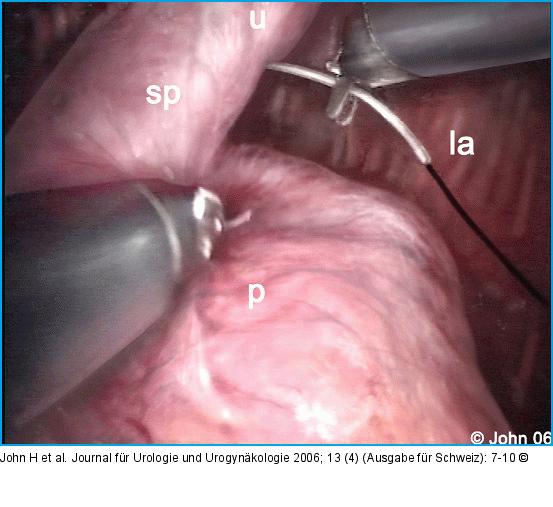

Abbildung 4a-i: DaVinci-Prostatektomie - Technik Die endopelvine Faszie wird beidseits inzidiert (a) und der Plexus Santorini aus Hämostasegründen durchstochen (b). Der Blasenhals wird schonend abgesetzt (c), die Adnexe abgesetzt (d) und die Prostata nach Eröffnen der Denovillierschen Faszie (e) vom Rektum abgeschoben. Die neurovaskulären Bündel werden nach Möglichkeit geschont (f). Apikal wird ein möglichst langer Harnröhrenstumpf gebildet (g) und das Präparat abgesetzt. Nach der vesiko-urethralen Anastomose (h) kann die Prostata über einen Endobag durch den infraumbilikalen Zugang geborgen werden (i). |

Die endopelvine Faszie wird beidseits inzidiert (a) und der Plexus Santorini aus Hämostasegründen durchstochen (b). Der Blasenhals wird schonend abgesetzt (c), die Adnexe abgesetzt (d) und die Prostata nach Eröffnen der Denovillierschen Faszie (e) vom Rektum abgeschoben. Die neurovaskulären Bündel werden nach Möglichkeit geschont (f). Apikal wird ein möglichst langer Harnröhrenstumpf gebildet (g) und das Präparat abgesetzt. Nach der vesiko-urethralen Anastomose (h) kann die Prostata über einen Endobag durch den infraumbilikalen Zugang geborgen werden (i). |